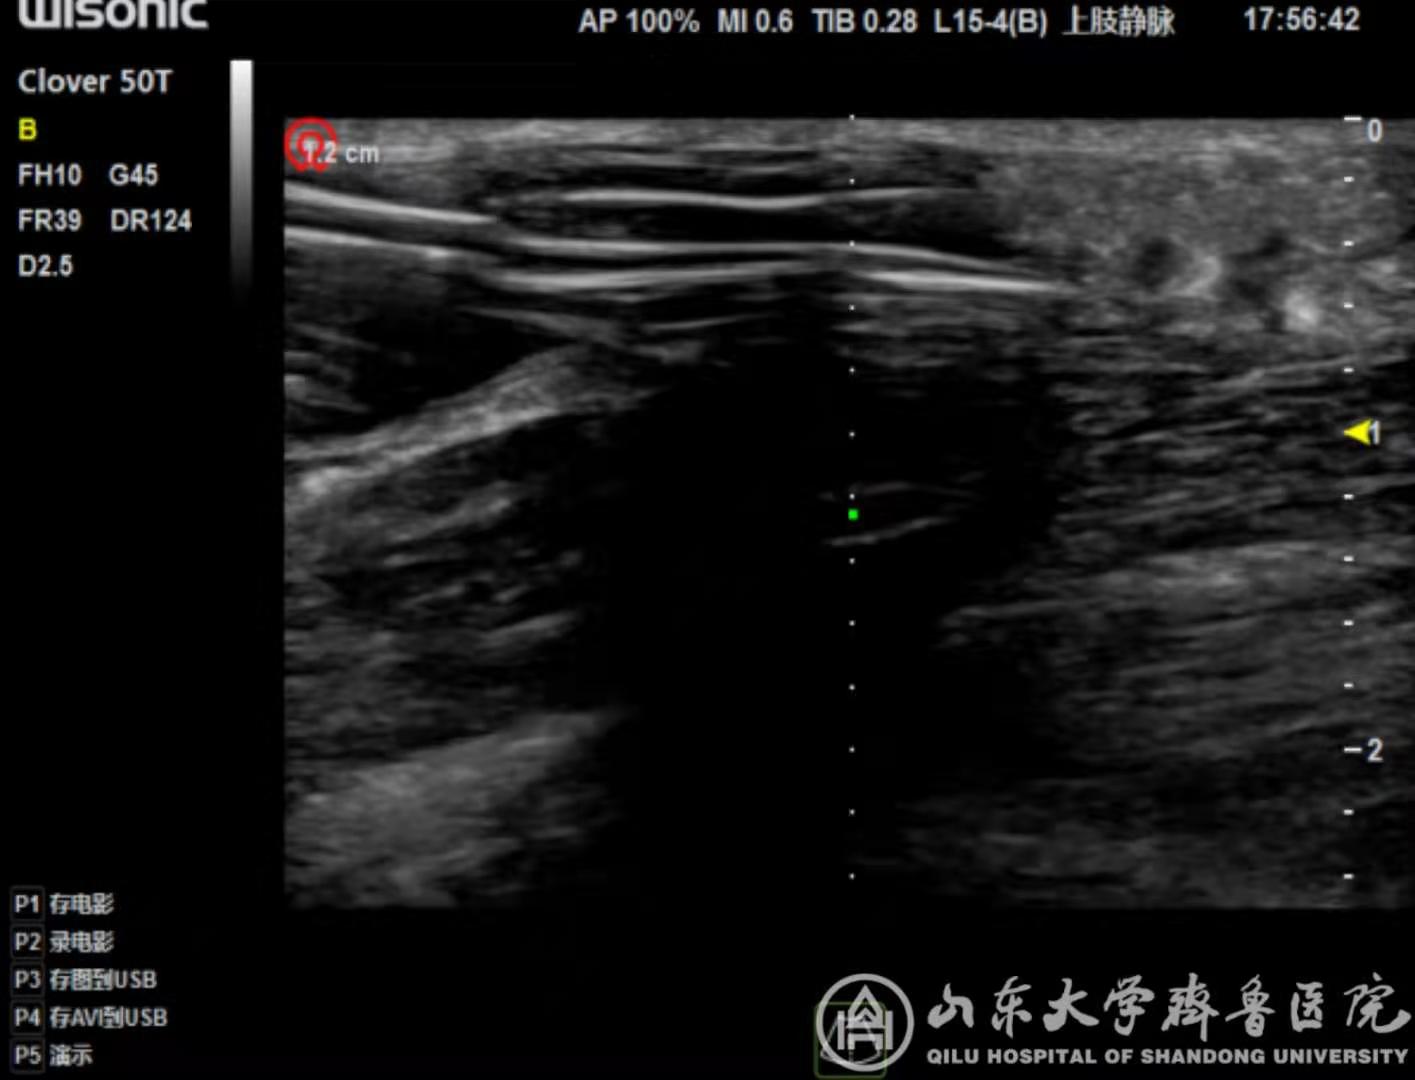

【本站讯】近期,绿帽社 血液净化科在田军主任医师指导下,由郭宁主治医师完成两例B超引导下即穿性人工血管腔内PTA开通手术。

目前随着透析患者数目的增多和透析技术的进步,透析患者生存期逐渐延长,因此构建可长期使用的血管通路是对于透析患者长期生存至关重要的问题。由于血管本身的变异,加之很多肾衰患者合并高血压及糖尿病,有部分患者血管条件差,不存在建立自体内瘘的条件,因此人工血管(AVG)是该类患者重要的重要通路。但人工血管并非自体结构,存在血栓、狭窄等可能性亦较自体血管的概率高,一旦出现血栓,人工血管将失去功能,需要紧急开通。即穿型人工血管有三层结构,若无B超引导盲目穿刺,可能穿到中层或后壁,风险较正常偏高。相较传统手术方式,B超引导腔内开通术具有患者损伤少,见效快,无放射损伤等优势。

清晰的B超影像为手术提供了精确指引

近期完成的两例B超引导下即穿性人工血管腔内PTA开通手术,该类手术可日间完成,手术后可即时使用,避免过度期插管,处于省内先进水平,标志着我院对AVG有良好的维护能力,为广大肾衰患者健康带来了福音。